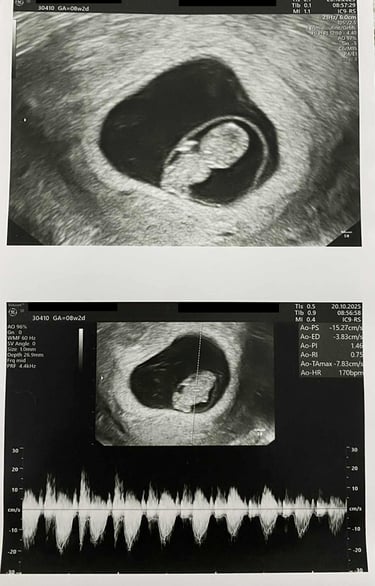

Today is probably one of the most memorable days of my life. I saw you for the first time. Yes, probably not in flesh and bones, but in a negative photo.

We had our first ultrasound today. The doctor took us into the room and told me to look at the screen. And there you were, a tiny human being sleeping peacefully in your mother’s womb. She then played your heartbeat. It was the most pleasant sound on earth. I didn’t even realize I was weeping. Thanks to Allah for blessing me with such a moment.

The doctor then checked your mother’s health and other reports, and everything seemed okay.

There you are, my tiny bundle of joy.